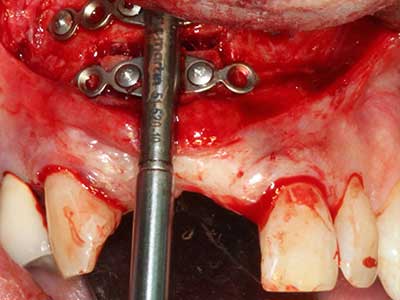

Purely orthodontic indications include orthognathic surgery, genioplasty (Fig. 27-30) and orbital decompression in patients with advanced endocrine orbitopathy as a result of Basedow’s disease (Ponto, Zwiener et al. 2014). Piezo devices are also used in maxillofacial surgery and to remove tumours at the base of the skull in various hospitals.